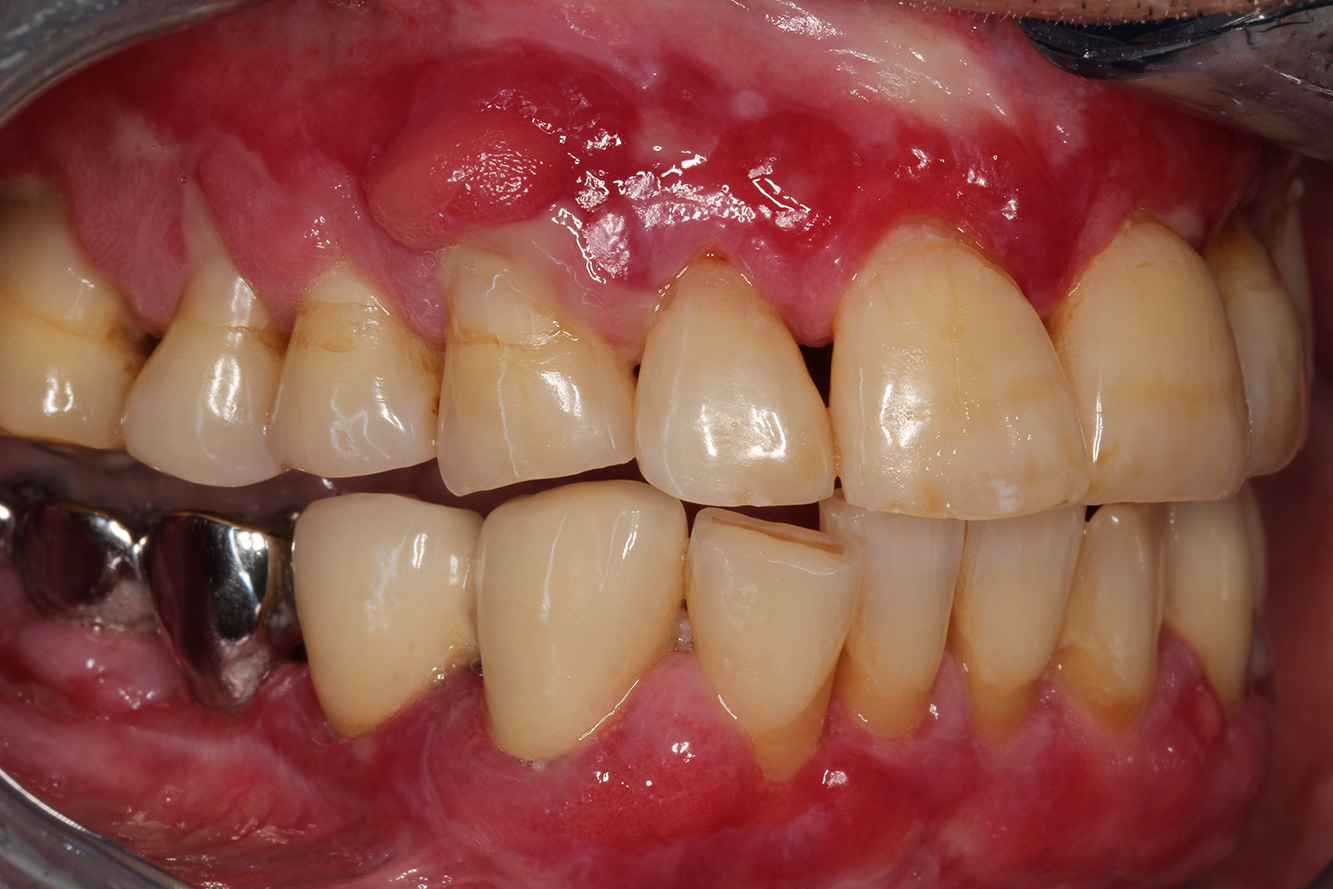

Se presenta un paciente de 71 años con trasplante de riñón e hipertensión (presión arterial alta). Debido a su historia médica, es necesario el tratamiento continuo con ciclosporina para suprimir el sistema inmunitario y amlopidina para bajar la presión arterial. Además, el paciente relata encías sensibles y sangrantes. Desde el punto de vista de la salud oral, hay dientes restaurados con ocho piezas faltantes, hiperplasia gingival pronunciada, periodontitis en fase II, de grado B con bolsas activas y una caries inicial en la pieza 22. En la evaluación del riesgo de caries se ha establecido un riesgo de caries medio (API 60). Para la sesión de profilaxis se hacen las siguientes recomendaciones.

Con base en la historia médica, se detecta un riesgo de complicaciones importante. Debido al trasplante de riñón, el paciente está inmunodeprimido (ciclosporina), también tiene el sistema inmunitario debilitado y necesita profilaxis para infecciones (recomendación: 2 g de amoxicilina como antibiótico 1 h antes de la sesión). Al mismo tiempo, el tratamiento continuo hace que el paciente tenga un mayor riesgo de enfermedad, dado que la hiperplasia gingival establecida está asociada a la medicación (20).

Se debe abordar la situación del paciente, especialmente cuando se trata de motivación y aprendizaje. La hiperplasia gingival dificulta la higiene oral en casa. La mayor susceptibilidad a las infecciones y el progreso y la nueva formación de hiperplasias (22) debe hablarse de igual a igual. Al mismo tiempo, deben explicarse las técnicas de higiene adecuadas según las necesidades individuales.